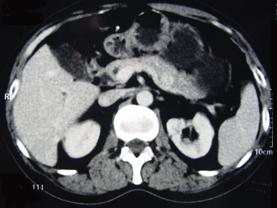

问题 男性,57岁,1年前无明显诱因反复出现嗜睡及发作性神志不清,进食糖水或甜品后症状即缓解,腹部CT检查如下图,最佳的诊断是()

选项 A.胰腺癌 B.胰岛细胞瘤 C.胰腺转移瘤 D.胃泌素瘤 E.舒血管活性肽瘤

答案 B